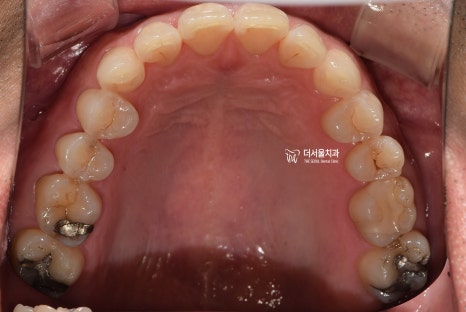

『1. 치아 상태 확인』

정면, 측면, 교합면 등 여러가지 방향에서

환자가 가지고 있는 치열의 상태를 먼저 확인합니다.

삐뚤빼뚤한 곳은 있는지, 또는 거꾸로 물리는 곳은

없는지, 나아가 충치 및 염증을 가지거나

치아 이동에 방해가 될 수 있는 사랑니를

가지고 있는지, 결손치나 있는지 등을

면밀하게 살펴보게 됩니다.